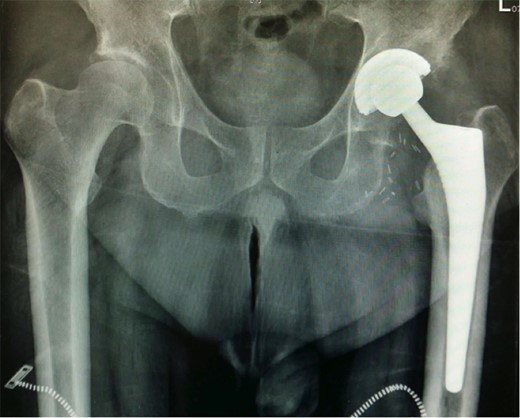

Surgery was subsequently undertaken using hydroxyapatite-coated cementless femoral implant and corresponding modular acetabular component. (Fig. 2). The surgery was uneventful, peri-operative course without complication, and post-operative review showed a successful resolution of his symptoms. Intraoperatively, the excised femoral head was sent for screening for bone harvest.